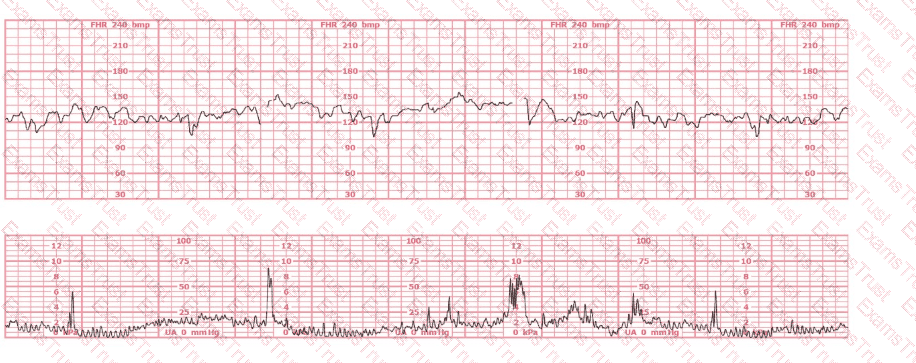

This fetal heart rate tracing is from a woman in the second stage of labor. This tracing is best interpreted as:

The decelerations seen in the fetal monitoring tracing shown are best described as:

This tracing reflects

The fetal heart rate tracing shown represents